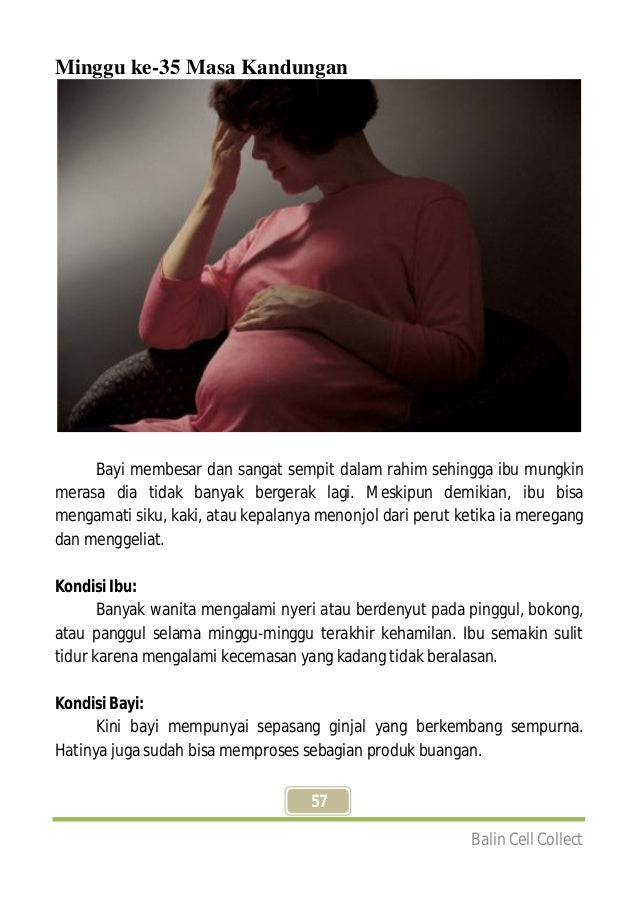

Tahapan Perkembangan Janin: Minggu ke-35

Tahapan Perkembangan Janin: Minggu ke-35